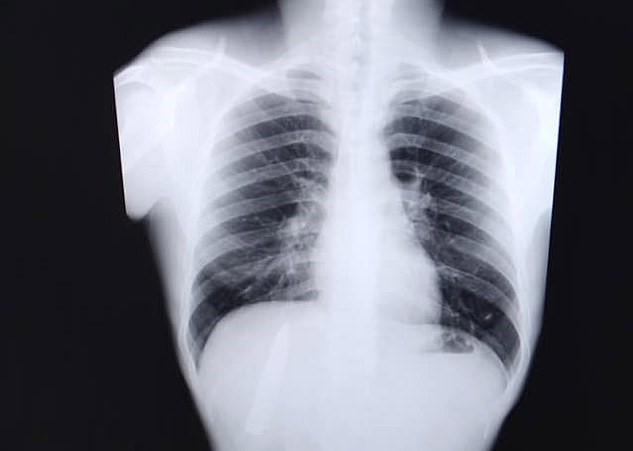

The 25-year-old was shocked to learn that the blade of the knife was still in his body and very close to his lungs.